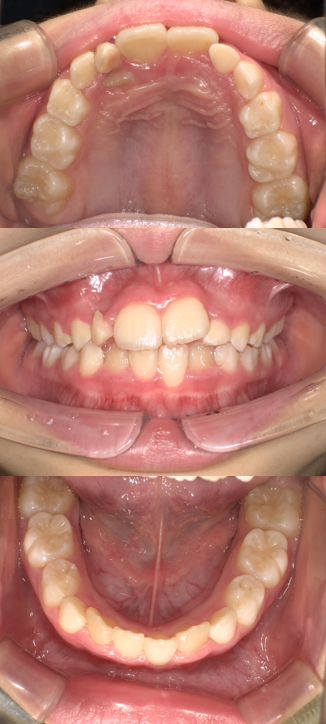

BEFORE

年齢:9歳 女の子

主訴/治療内容:

お子様の歯並びが気になり、他院様でプレオルソの治療を開始したが、改善する見込みがなくご相談に来られました。現在まだ経過観察途中ですが、当院でプレオルソ治療を開始して9ヵ月でこれだけ歯並びが改善されました。装置は寝ている間に装着するだけです。早期に治療を開始することで、将来的な矯正を未然に防ぎ、経済的負担・治療の負担を大幅に軽減することが可能になります。同様のケースで少しでも気になっていらっしゃいましたら、是非お気軽にご相談ください。

治療期間/通院回数:プレオルソ装着9ヵ月 経過観察途中

費用: 精密検査・診断料 71,500円  0期治療 55,000円